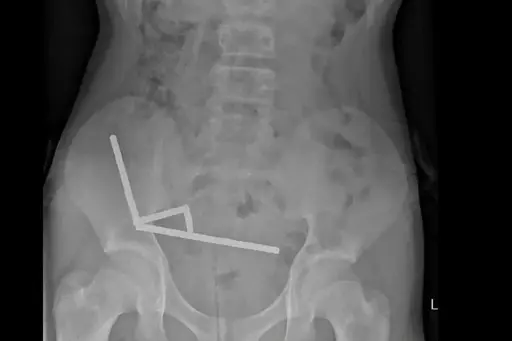

An X-ray showed the magnets had clumped together in four straight lines inside the child’s intestines.

“These appeared to be in separate parts of bowel adhered together due to magnetic forces,” they said.

I kinda get it. These things come as a cylinder. He didn’t so much swallow 100 individual magnets, but rather swallowed a complete cylinder package of them. The x-ray tends to confirm that.